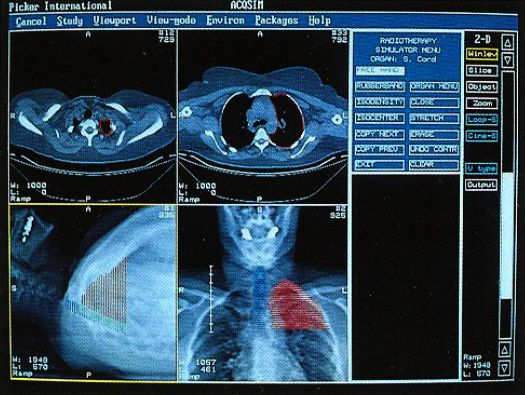

Picker International (Cleveland, Ohio) was one of the major manufacturers of medical imaging equipment, having started as an X-ray machine company in 1909. They expanded to high tech imaging modalities including Computed Tomography (CT or CAT), Magnetic Resonance Imaging (MRI), Positron Emission Tomography (PET), ultrasound, and others, while still providing basic (but modern) X-ray equipment. In the early 1990s Picker needed a platform for a radiation treatment planning system that was being developed to go along with their high-end CT scanners. They became interested in the DDD technology to provide a competitive advantage and gave us some additional funding (while still DDD) to support the effort. Now with Picker, everything had to have a "Q" in the name - standing for quality or something. So after some repackaging and design enhancements including optimization for ray tracing, what would probably have been called Voxelscope III (VS3) became the VoxelQ (or simply "VQ") to be incorporated into the AcQSim or AcQPlan treatment planning system, and to be bundled with high-end CT scanners, among others.

Here are typical examples of VoxelQ displays. These are mostly only windows, not the full screen which is more along the lines of the last block of AcQSim photos.

VoxelQ Multiplanar Reformatting (Axial, Saggital, Coronal, Curved)

VoxelQ Shaded Surface

VoxelQ Volume Rendering

VoxelQ Segmentation

VoxelQ Virtual Endoscopy

AcQSim Screen Examples